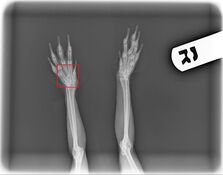

- V. Sjöberg. Ventro-dorsal radiography of the left hind foot with a broken toe